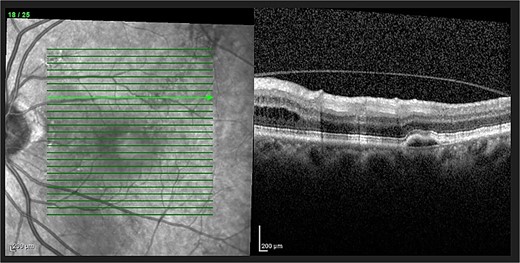

Optical coherence tomography (OCT) demonstrated an atrophied right macular. Whilst the left eye showed a thickened choroid, multiple pigment epithelial detachments (PED), subretinal fluid and intraretinal fluid nasally. This is shown in Figs 2 and 3.

(A) OCT of left eye – IRF and SRF with serous retinal detachment. Choroidal thickness = 454 μm.

The diagnosis of CSCR was made by the patient’s ophthalmologist, meeting diagnostic criteria as seen in Table 1. The patient meets major criteria with an OCT showing serous retinal detachment, and RPE alterations seen in Figs 2 and 3, respectively. Figure 2 displays a subfoveal choroidal thickness of 454 μm meeting the minor criteria.